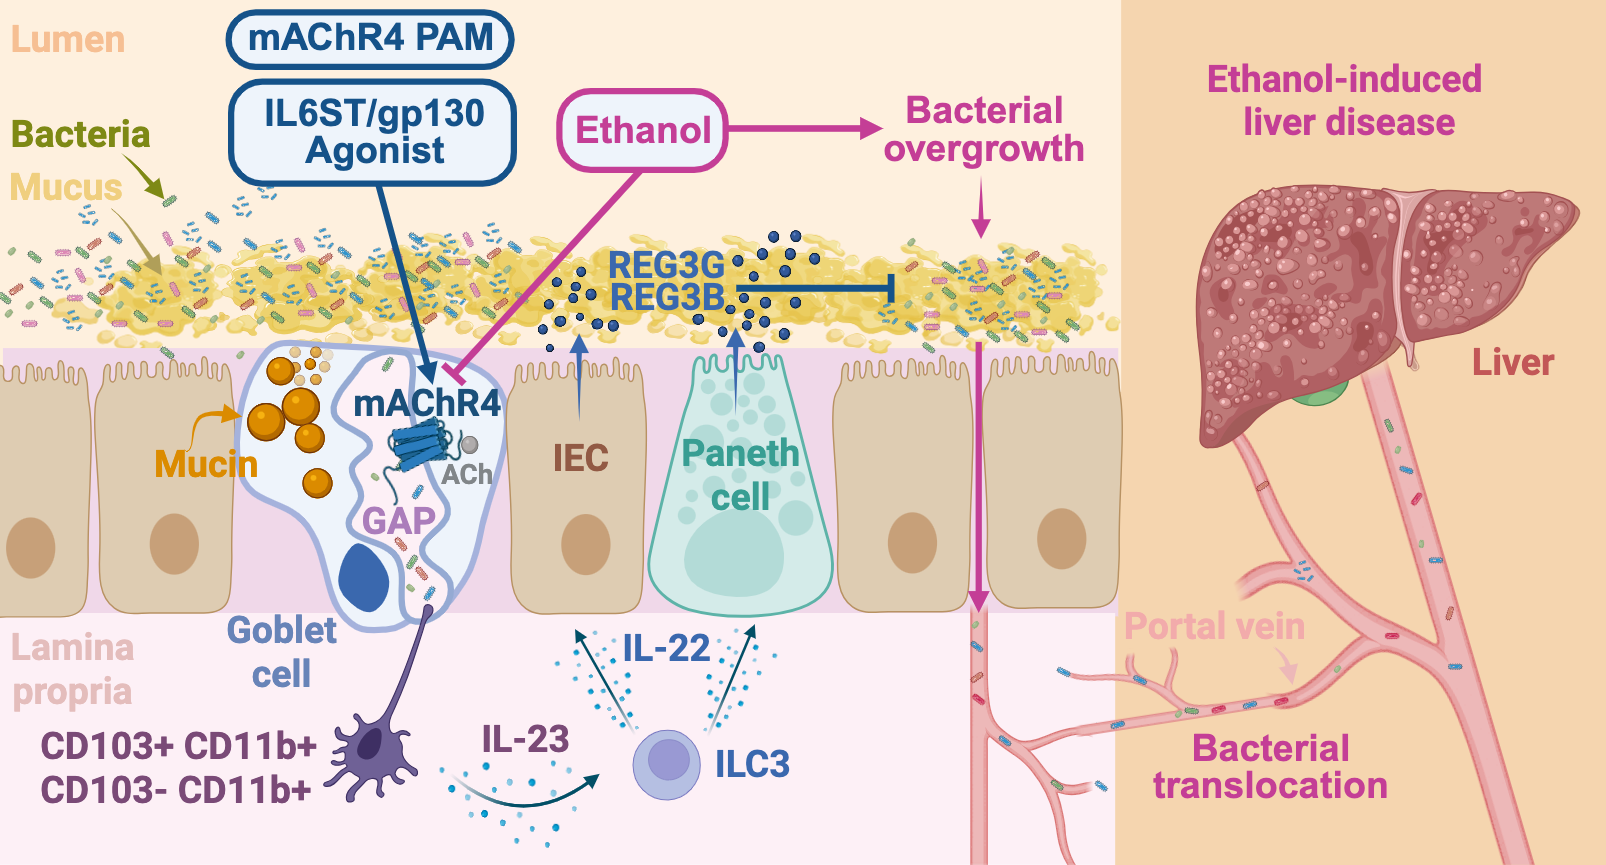

Our work: mAChR4 suppresses liver disease via GAP-induced antimicrobial immunity

Our study reveals a critical mechanism by which small intestinal GAPs, formed in response to mAChR4 activation, are essential for maintaining mucosal immune surveillance and limiting microbial translocation to the liver.

-

Alcohol Disrupts mAChR4-GAP-Mediated Barrier Function. Chronic alcohol exposure in both humans and mice downregulates mAChR4 expression and related pathway transcripts, leading to reduced GAP formation. mAChR4 downregulation strongly correlates with ALD progression in patients with AUD. Our preclinical models demonstrate that GAP closure is mediated through MAPK. This impairs barrier function by disrupting antigen sampling by LP-APCs, weakening antimicrobial immunity (REG3), and facilitating pathogenic bacterial translocation, a key driver of ALD progression.

Alcohol reduces mAChR4 and GAP formation. Figure from Llorente et al., Nature, 2025

-

GAP-Induced Immune Cascade Restores Protection. We define a novel and critical molecular mechanism involving GAP generation, which samples luminal antigens and initiates a protective, APC-mediated immune response. APCs secrete IL-23, promoting IL-22 production by ILC3s. IL-22 then acts on IECs and Paneth cells to induce antimicrobial Reg3 lectins. In summary, the GAPs → LP-APCs → IL-23 → ILC3s → IL-22 → Reg3 axis limits mucosa-associated bacteria, prevents bacterial translocation to the liver, and protects against ethanol-induced liver injury.

GAPs deliver luminal antigens to lamina propria antigen-presenting cells, educating the intestinal immune system and stimulating REG3B/G antimicrobial peptides. Figure created with a license from BioRender. -

Intestinal IL6ST-Induced GAP Formation. Using genetic models with IEC-specific IL6ST activity either increased (gain-of-function) or decreased (loss-of-function), combined with a sophisticated co-culture system of small intestinal organoids and enteric neurons, we demonstrate that IL6ST/gp130 signaling promotes GAP formation through activation of the mAChR4 pathway.

Co-cultured mouse SI organoids with enteric neurons. Figure from Llorente et al., Nature, 2025 - mAChR4 Pathway Induction Prevents ALD. Activating mAChR4, chemogenetically, or via IL6ST signaling, restores this immune cascade circuit, reduces bacterial translocation, and prevents ethanol-induced steatohepatitis.

- First Demonstration of the Protective Role of GAPs in ALD. Our goblet cell-specific manipulation of mAChR4 is the first to establish a direct immunoprotective role for GAPs in intestinal homeostasis and liver disease. These findings redefine goblet cells as key immune sentinels in the gut-liver axis and position GAP formation as a therapeutic checkpoint for ALD.

-

Selective AChR4 Positive Allosteric Modulation (AChR4 PAM), a promising therapy for ALD. Restoring GAP formation with an mAChR4 PAM prevents microbial translocation and ethanol-induced steatohepatitis in both WT and IEC-specific gp130-deficient mice, where disease is worsened.

Enhancement of GAP formation through IL6ST/gp130 activation, mAChR4 positive allosteric modulation (PAM), or chemogenetic GC-specific mAChR4 activation promotes expansion and function of antigen-presenting cells (APCs), strengthens gut barrier function, and prevents ethanol-increased mucosal bacteria and translocation through the GAP-APCs-ILC3-IL-22-REG3B/G axis, and Treg-mediated responses. Figure created with a license from BioRender. Figure from Llorente et al., Nature, 2025 -